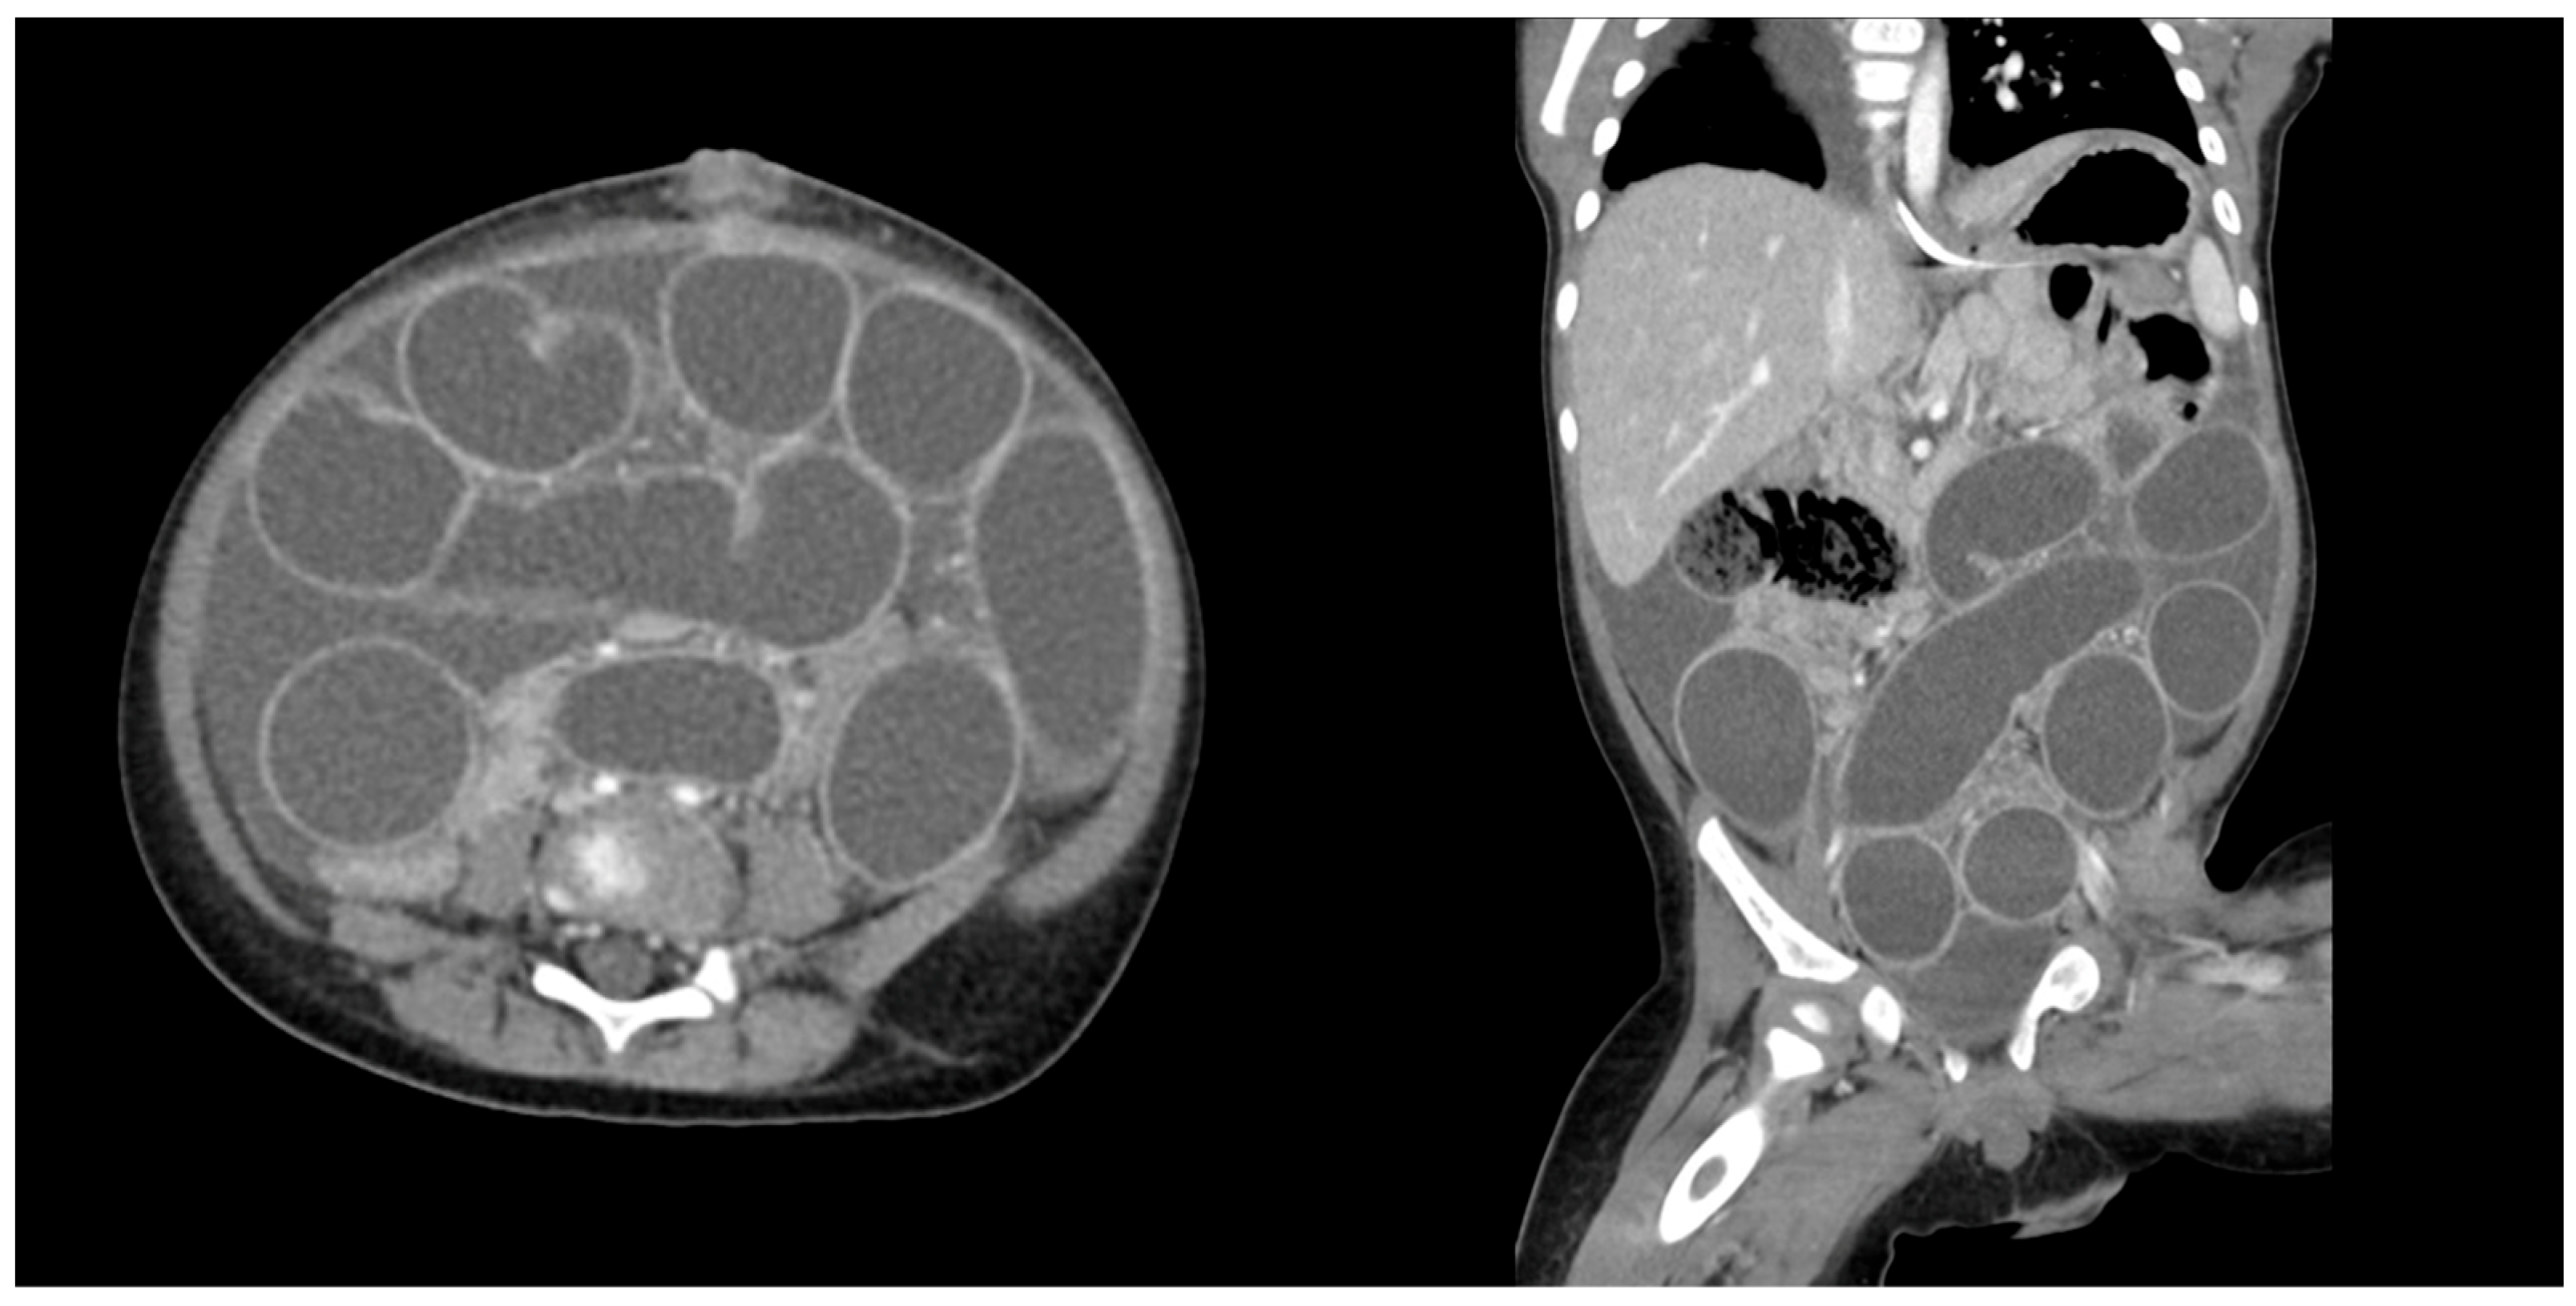

3.1. Patient 1

3.2. Patient 2

3.3. Patient 3